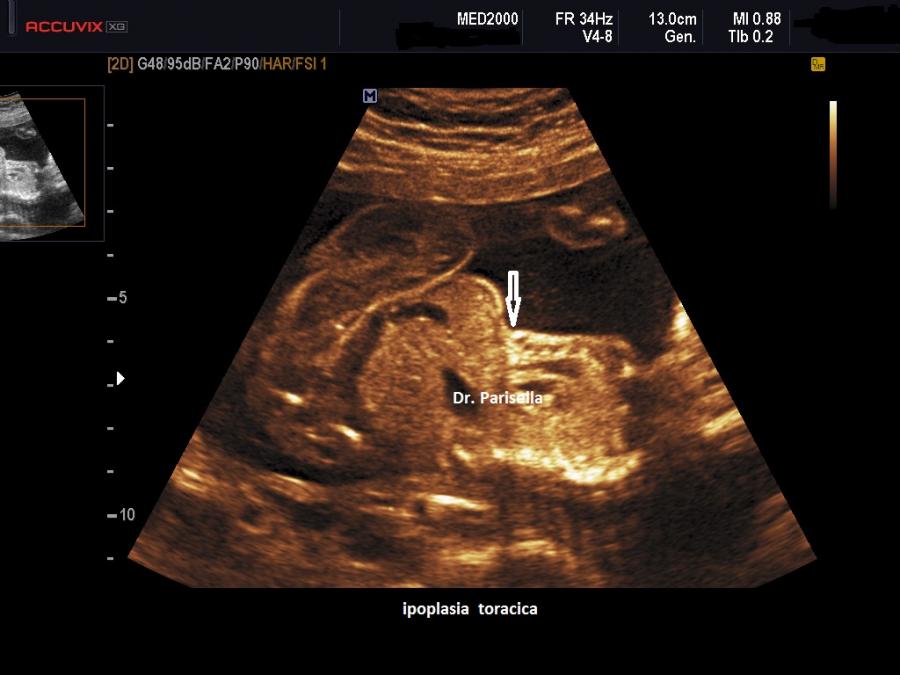

Le SRPS sono un gruppo di displasie scheletriche la cui caratteristica fondamentale è l'ipoplasia toracica. Fanno parte di questo gruppo anche la Distrofia Toracica Asfissiante o Sindrome di Jeune, la Displasia Condroectodermica o Sindrome di Ellis-van-Creveld e la Sindrome Campomelica. Il coinvolgimento del processo displasico delle coste e delle altre ossa della gabbia toracica porta ad una diminuzione delle dimensioni del torace con conseguente ipoplasia polmonare; l'ipoplasia polmonare a sua volta è la principale causa della morte nelle displasie scheletriche letali.

La MICROMELIA SEVERA e l’ IPOPLASIA TORACICA SEVERA (legata al torace stretto con coste corte) sono i segni principali presenti in tutte e quattro i tipi di SRPS e che indirizzano verso una corretta diagnosi. La POLIDATTILIA è presente nei primi due tipi, meno frequentemente nel tipo III, è assente nel tipo IV.

La MICROMELIA SEVERA e l’ IPOPLASIA TORACICA SEVERA (legata al torace stretto con coste corte) sono i segni principali che indirizzano verso una corretta diagnosi.